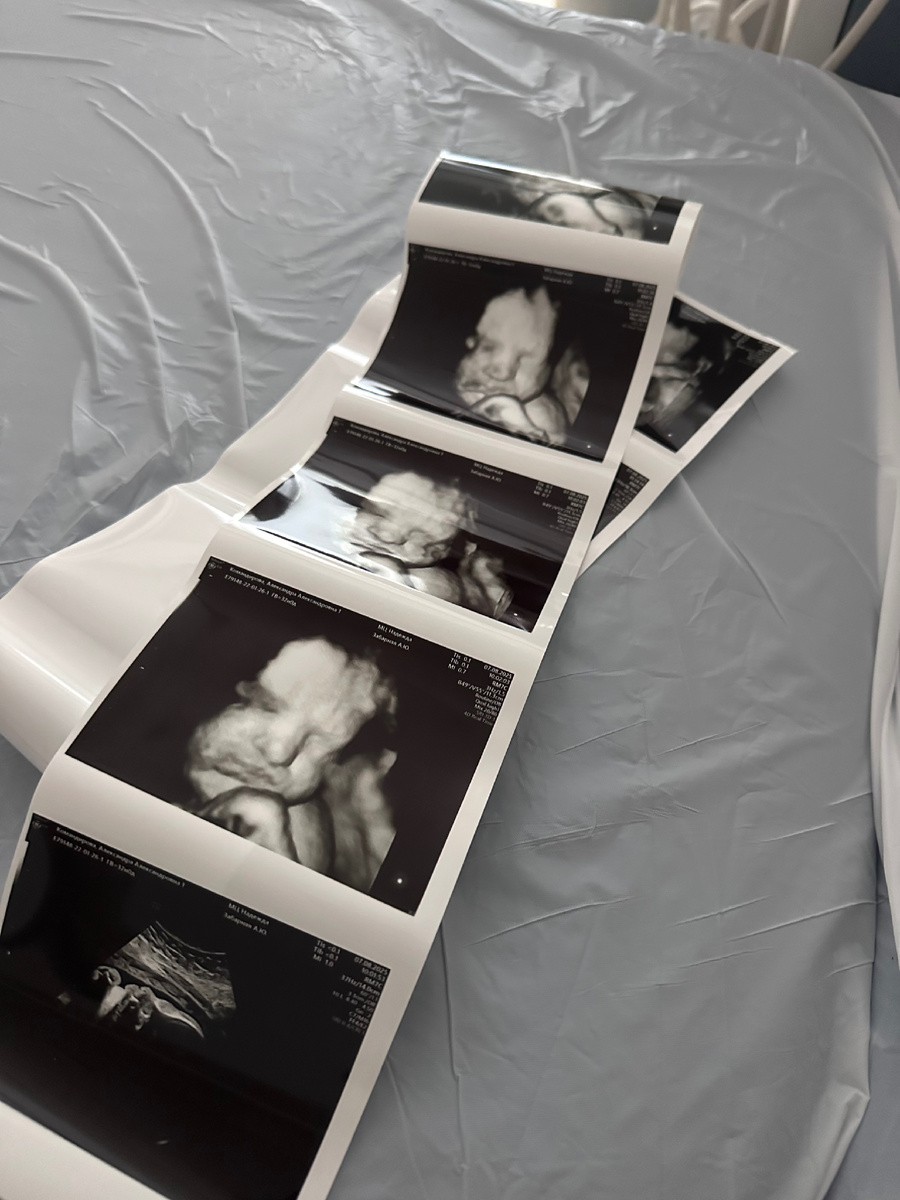

УЗИ 32 недели

Сегодня была на третьем скрининге, кроха показал наконец личико, до этого все наши «фото» были неудачными, в этот раз врач целую фотосессию провела, сказала, что вроде на меня похож. Посмотрим)) Развивается хорошо, набирает вес, уже 2 кг (без 39 грамм).